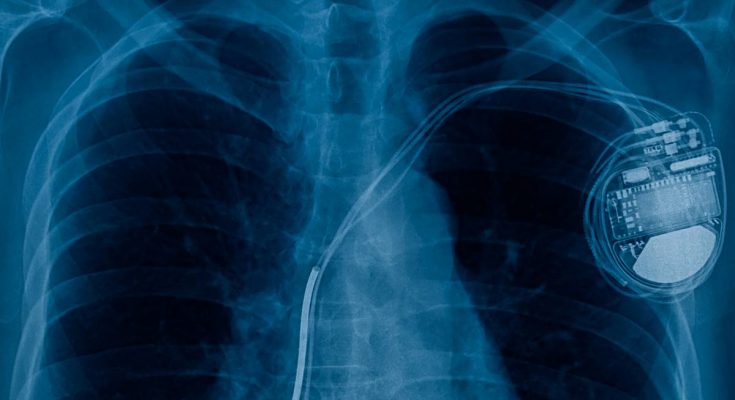

Με τον όρο «ιατροτεχνολογικά βοηθήματα» εννοούμε μία μεγάλη γκάμα εμφυτευμάτων, όπως αντλίες ινσουλίνης, βηματοδότες, ισχιακά εμφυτεύματα, ακόμα και σιλικόνη για το στήθος.